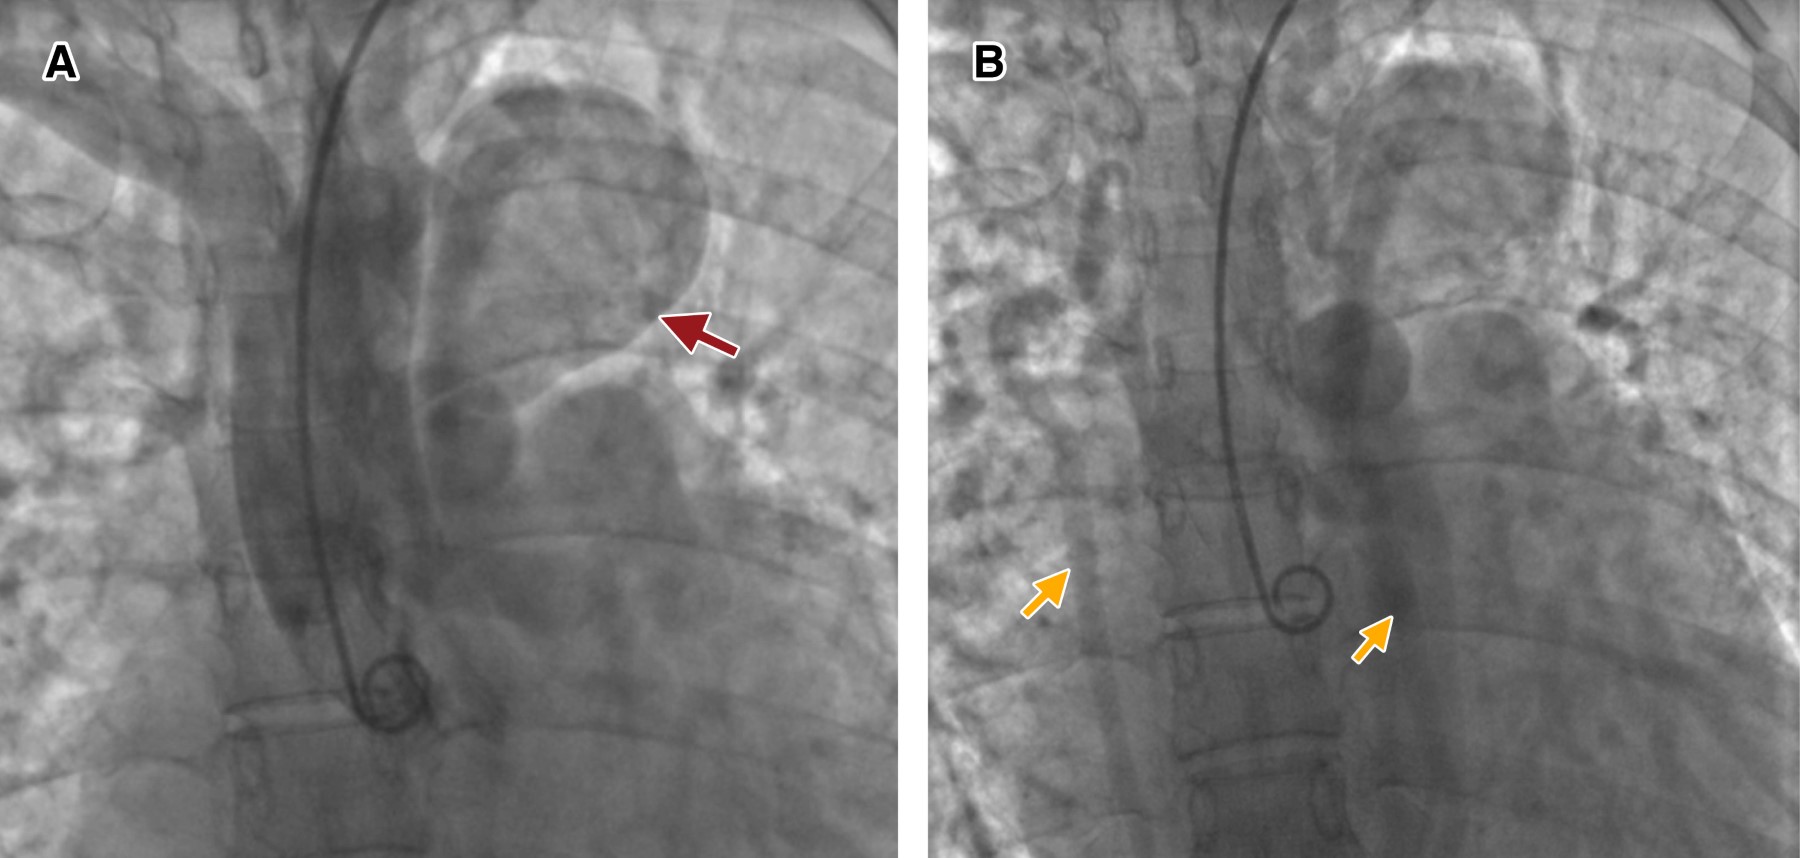

A first transthoracic echocardiogram was performed with generalized dilatation in the four chambers, decreased contractile dynamics, vena cava with diameters of 21 mm, distensibility of 33%. Subsequently, upon admission to our hospital unit in charge of cardiology, a second transthoracic echocardiogram was performed. Cardiomyopathy in dilated phase of undetermined origin, left ventricular systolic dysfunction with left ventricular ejection fraction of 43%, with abnormal global and segmental contractility due to global hypokinesia. Severe dilatation of the right chambers. Moderate mitral and tricuspid insufficiency, mild aortic insufficiency and severe pulmonary insufficiency. Severe pulmonary arterial hypertension due to pulmonary artery systolic pressure of 100 mmHg. Diagnostic cardiac catheterization was performed by interventional cardiology with the results of severe pulmonary arterial hypertension unresponsive to oxygen challenge, and an aortogram with anatomy compatible with common arterial trunk type I was performed (Figure 1). Angiotomography with reconstruction of large vessels was performed, where the interruption distal to the subclavian artery and an aneurysmal dilatation were identified (Figure 2). It was decided to evaluate the patient by the cardiac surgery service.

Figure 2